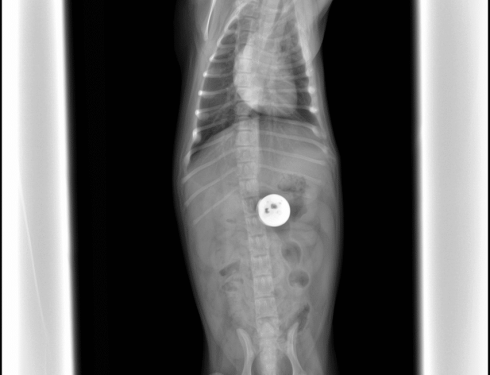

Two Broken Legs, One Bright Future: Esme’s Holiday Miracle